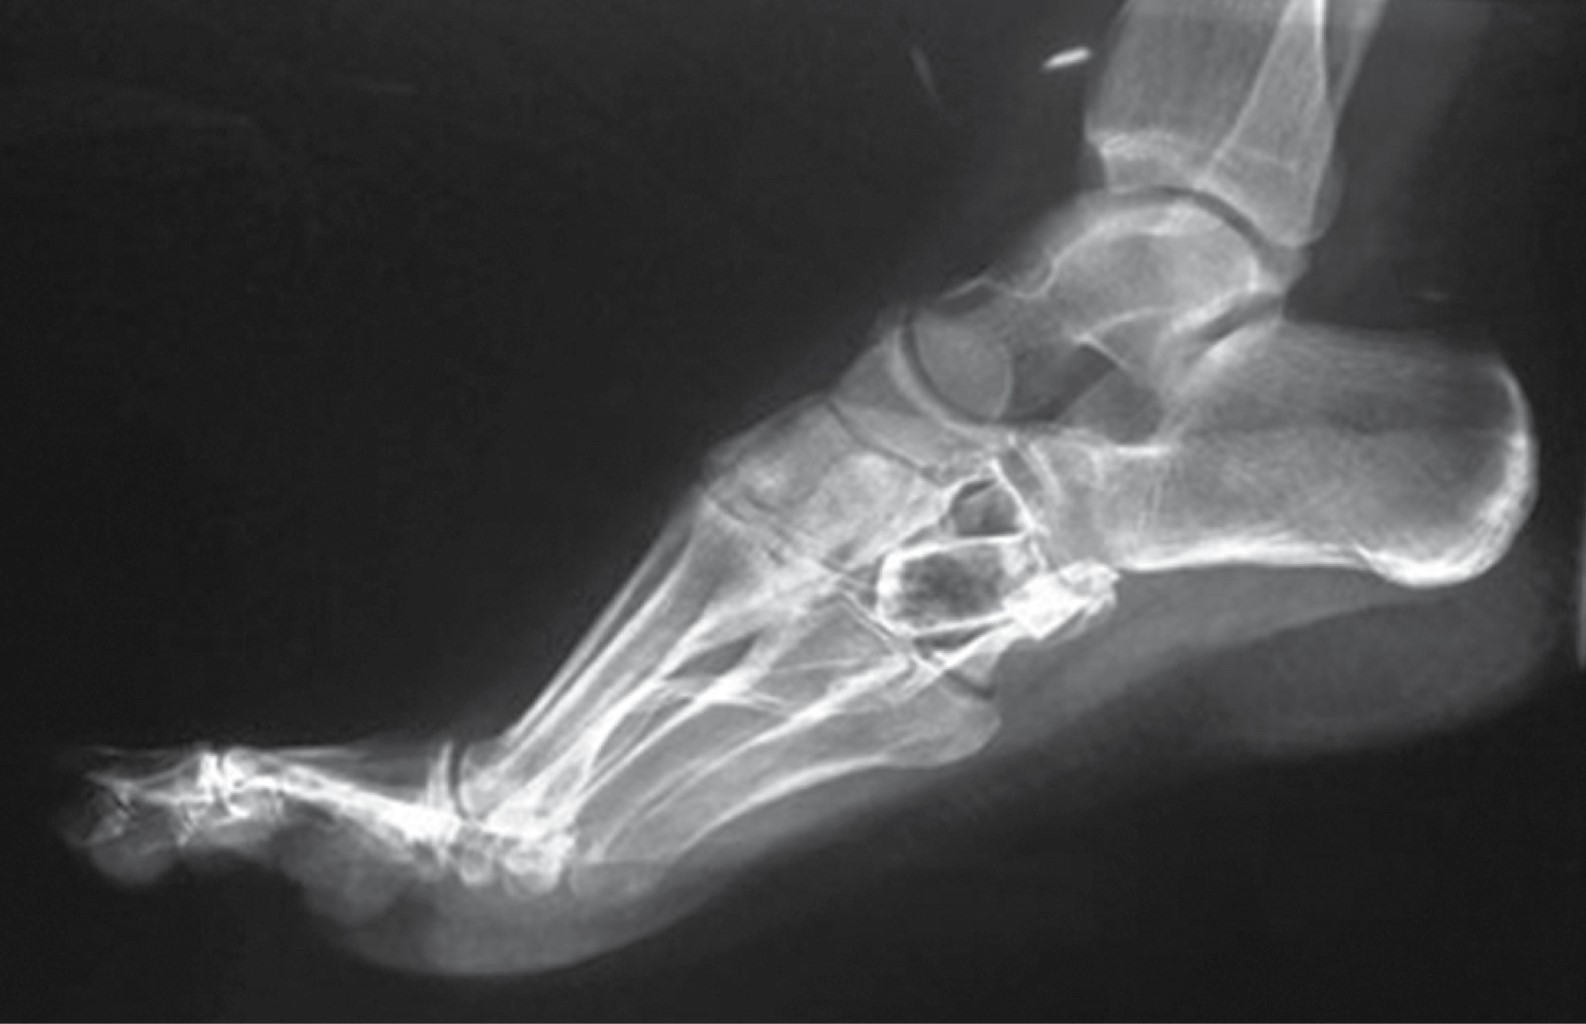

En las radiografías dorsoplantar y lateral de pie derecho se observa injerto óseo en el centro de una lesión en cuboides, radiotransparente, heterogénea, multilobulada, con bordes irregulares que sobrepasan la cortical lateral, multilobulados (Figuras 2 y 3).